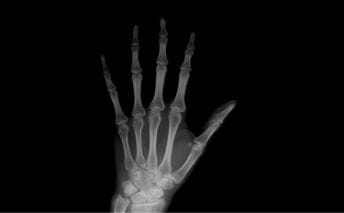

検査:レントゲン

CR(コンピューターX線撮影)は、X線を使って人間の透過像を作ります。各組織の1方向からの撮影のため、CT検査より短時間かつ低被曝での検査が可能です。

- 特長

- 短時間・低被曝